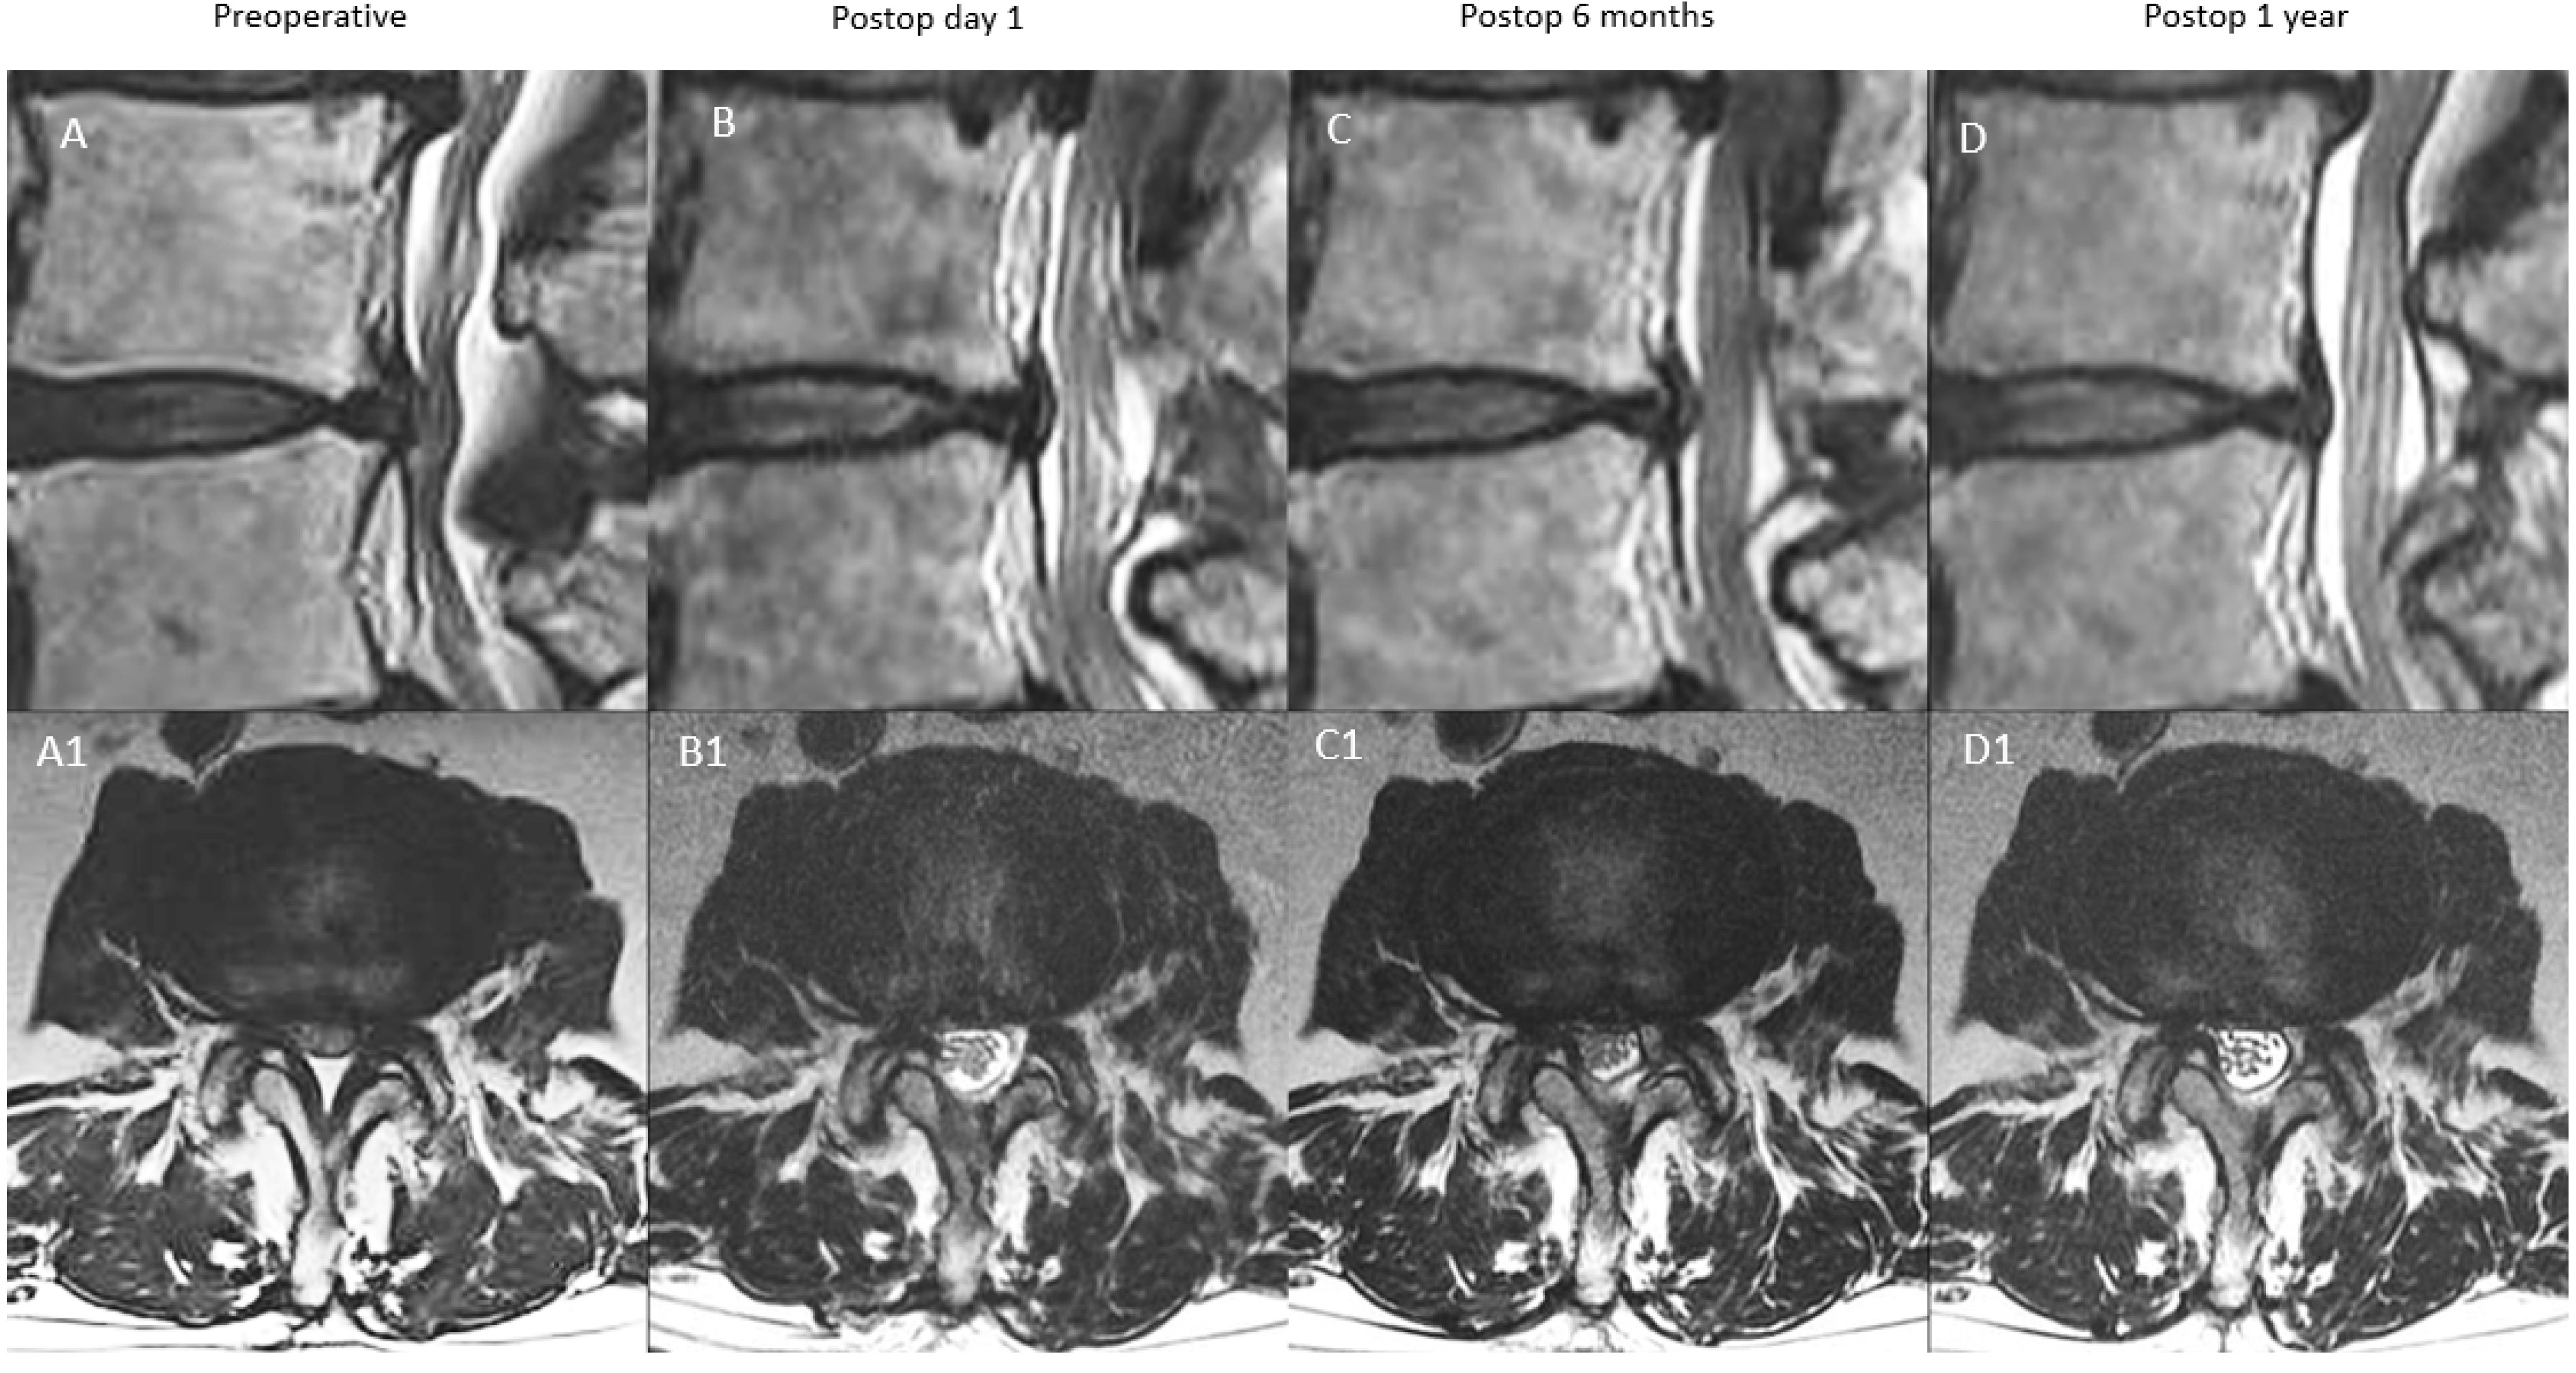

| A: Continuous Type | There is significant decompression with increased spinal canal area on postoperative day one, a modest drop at postoperative 6 months and close to postoperative 6 months value at postoperative one year | X | ≥70% X | 70–90% X (close to postoperative six months value) |

| B: Remodelling Type | There is significant decompression with increased spinal canal area on postoperative day one, a significant drop at postoperative 6 months and modest improvement at one year but less than 90% of the postoperative day one spinal canal area | X | <70% X | 70–90% X |

| C: Expansion Type | There is significant decompression with increased spinal canal area on postoperative day one, a modest drop at postoperative 6 months and significant improvement at one year with more than 90% of the postoperative day one spinal canal area | X | ≥70% X | 90–100% X |

| D: Restenosis Type | There is significant decompression with increased spinal canal area on postoperative day one, a significant drop at postoperative 6 months and minimal improvement at one year with <70% of the postoperative day one spinal canal area | X | <70% X | <70% X |